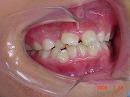

初診時

初診時より1年6カ月後 終了時(10歳9か月)

初診時より2年2カ月後

上下顎骨も拡大でき、咬み合わせの高さも改善できました。

今後、永久歯が萌出してから歯列矯正治療によってさらに美しい咬み合わせに改善していく事となります。